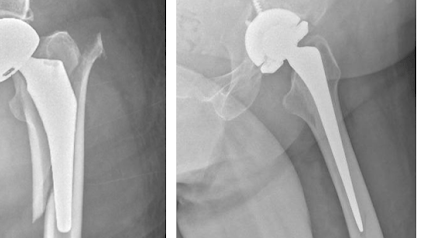

Existem prótese específicas para a revisão da prótese, que são mais robustas e revestidas com materiais especiais, como os metais trabeculados, que tem uma fixação excelente mesmo em ossos de má qualidade.

Materiais utilizados na revisão revisão de prótese de quadril.

Caso se confirme a soltura (também chamada de afrouxamento) da prótese, necessitamos fazer outra cirurgia, chamada de revisão de prótese, para retirada do componente solto e colocação de novo componente, geralmente de maior tamanho que o antigo, para garantir melhor fixação ao osso.